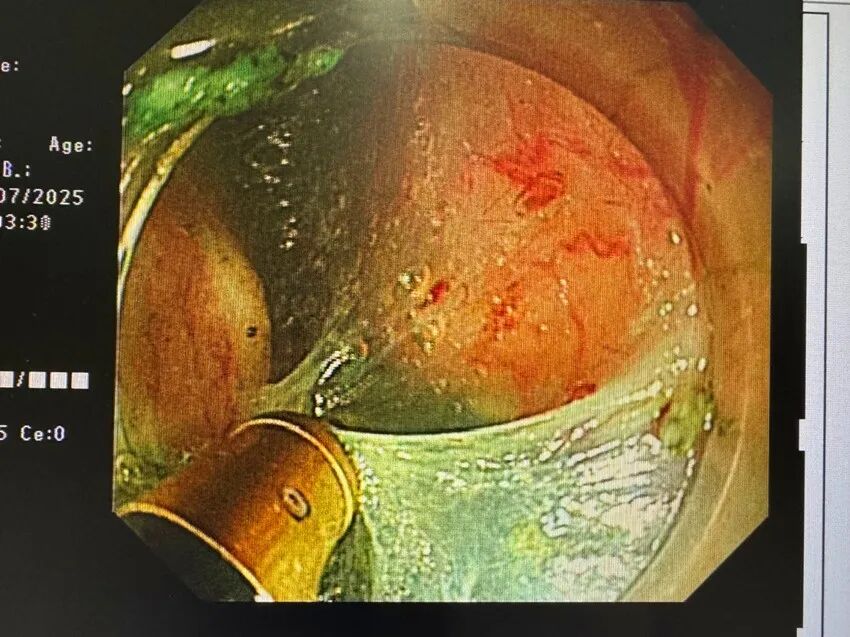

周密准备后,手术顺利开始,祝喜萍主任娴熟操作双极刀,小心翼翼地于患者食管黏膜下开辟“隧道”,最终在对起搏器未造成干扰的情况下,精准剥离肿瘤。双极刀尤其发挥关键作用,其闭合回路设计将电流严格限制在局部组织,有效避免了对邻近起搏器的电磁干扰。整个手术过程平稳顺利,耗时不足一小时,肿瘤被完整切除,同时最大程度保护了食管黏膜的完整性。

祝喜萍主任对此表示,内镜隧道技术(STER)是一种先进的内镜微创手术方法,通过在消化道黏膜下层建立“隧道”到达固有肌层病变,完整切除肿瘤的同时能有效保护黏膜表面,减少穿孔和术后狭窄风险。而双极刀电回路局限于局部组织,热损伤深度控制在单极刀80%以内,适用于食管/结肠等薄壁部位、高龄或合并植入式电子设备患者。两者相得益彰,为相关患者康复共同保驾护航。